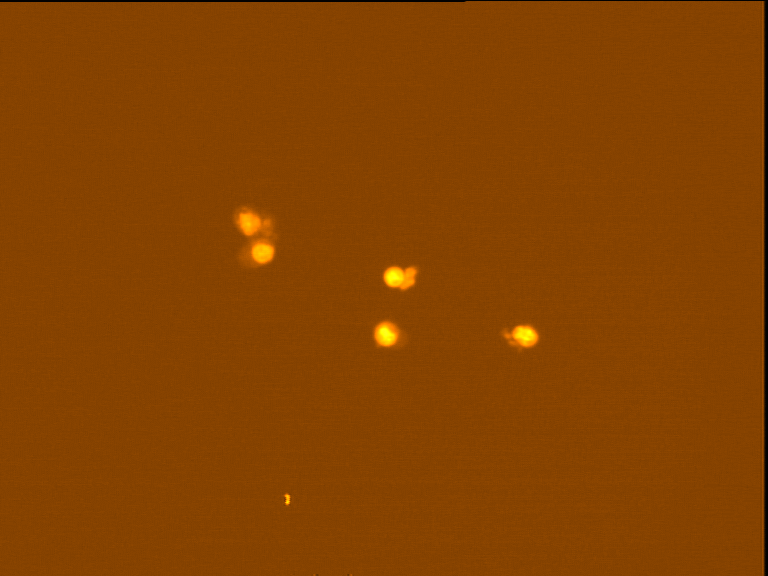

Fig. 4 through 6 show the morphological features of Raji cell sub-lines exposed to DOX, indomethacin, or verapamil. Some of the reversal agents significantly increased the frequency of apoptotic cells compared with control cells. Thus, the P-gp reversal agents were able to overcome apoptotic resistance in the NHL cell-line model. Apoptotic cells in the controls contributed approximately 10% of the whole population (i. e., 61/600 x 100 = 10.16% for TK+ and 69/600 x 100 = 11.5% for TK-). After exposure to the P-gp reversal agents, apoptic cells increased to 22.3% with indomethacin and to 43% with doxorubicin in TK+ cells. In TK- cells, apoptic cells increased from 11.5% to 26.8% and 75.7% with indomethacin and doxorubicin, respectively.

Fig. 5: Morphological features of Raji TK+ cells after treatment with indomethacin (1), verapamil (2) and DOX (3). In each row, left images show intact cells, middle images show apoptotic cells, and right images show necrotic cells as they appeared under the microscope X 200

Fig. 6: Morphological features of Raji TK- cells after treatment with indomethacin (1), verapamil (2), and DOX (3). In each row, left images show intact cells, middle images show apoptotic cells, and right images show necrotic cells as they appeared under the microscope X 200